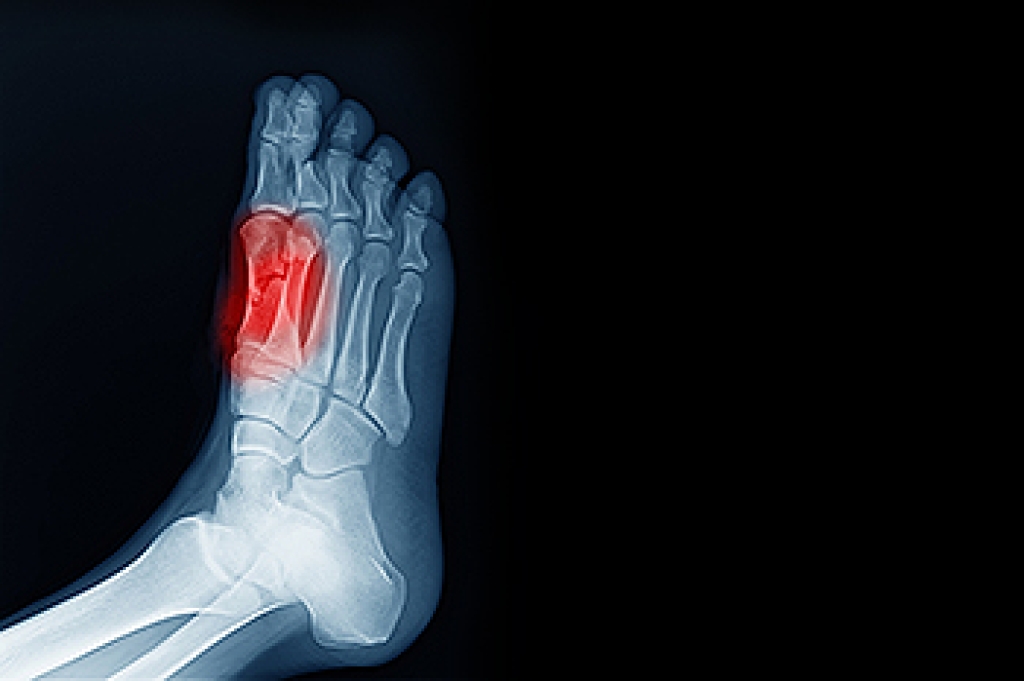

Sesamoiditis involves inflammation of the tendons that surround two small bones located beneath the big toe joint. These sesamoid bones help bear weight and assist with movement, but repetitive stress from running, dancing, or wearing tight shoes can irritate them. People with sesamoiditis often experience a dull, aching pain under the ball of the foot that worsens with activity. The big toe may become stiff or painful to move, and, in some cases, swelling or bruising can develop. A podiatrist can evaluate pain under the toe by checking joint movement and using X-rays or MRI scans to confirm inflammation or rule out fractures. If symptoms do not improve, a podiatrist may suggest orthotic shoe inserts, or, in rare cases, surgery to remove one of the bones. Preventing long-term joint damage requires early diagnosis and care. If you have pain under the big toe, it is suggested that you schedule an appointment with a podiatrist for an exam and appropriate treatment.

Sesamoiditis is a condition of the foot that affects the ball of the foot. It is more common in younger people than it is in older people. It can also occur with people who have begun a new exercise program, since their bodies are adjusting to the new physical regimen. Pain may also be caused by the inflammation of tendons surrounding the bones. It is important to seek treatment in its early stages because if you ignore the pain, this condition can lead to more serious problems such as severe irritation and bone fractures.